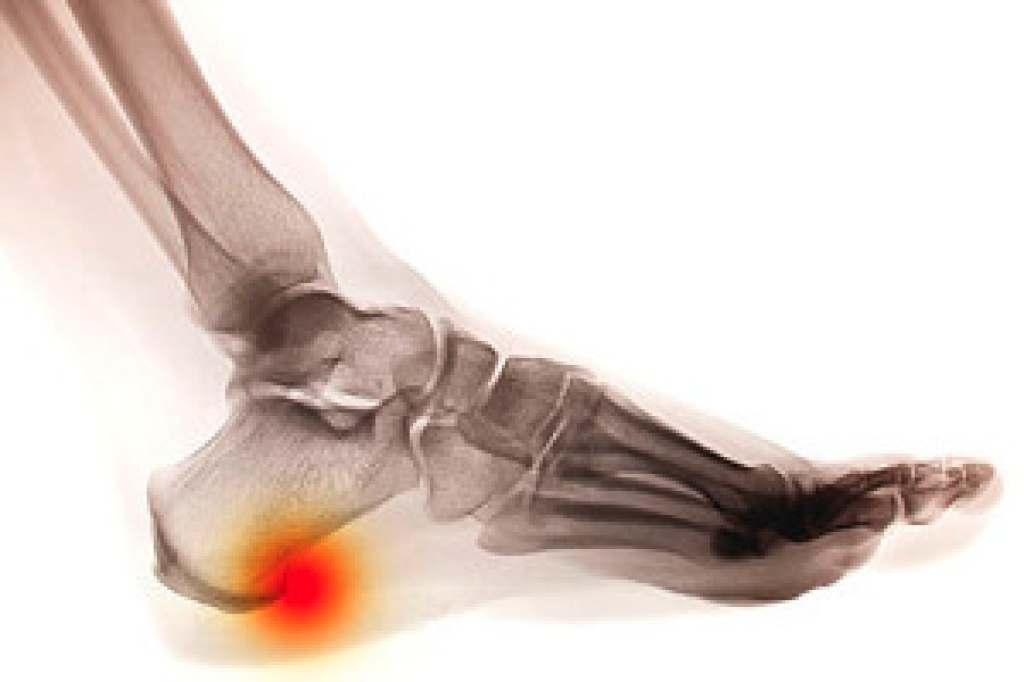

Most Common Injuries

People who are active or athletes are prone to a variety of injuries. Therefore, it is often important to take part in physical therapy in order to quickly get back on the right track.